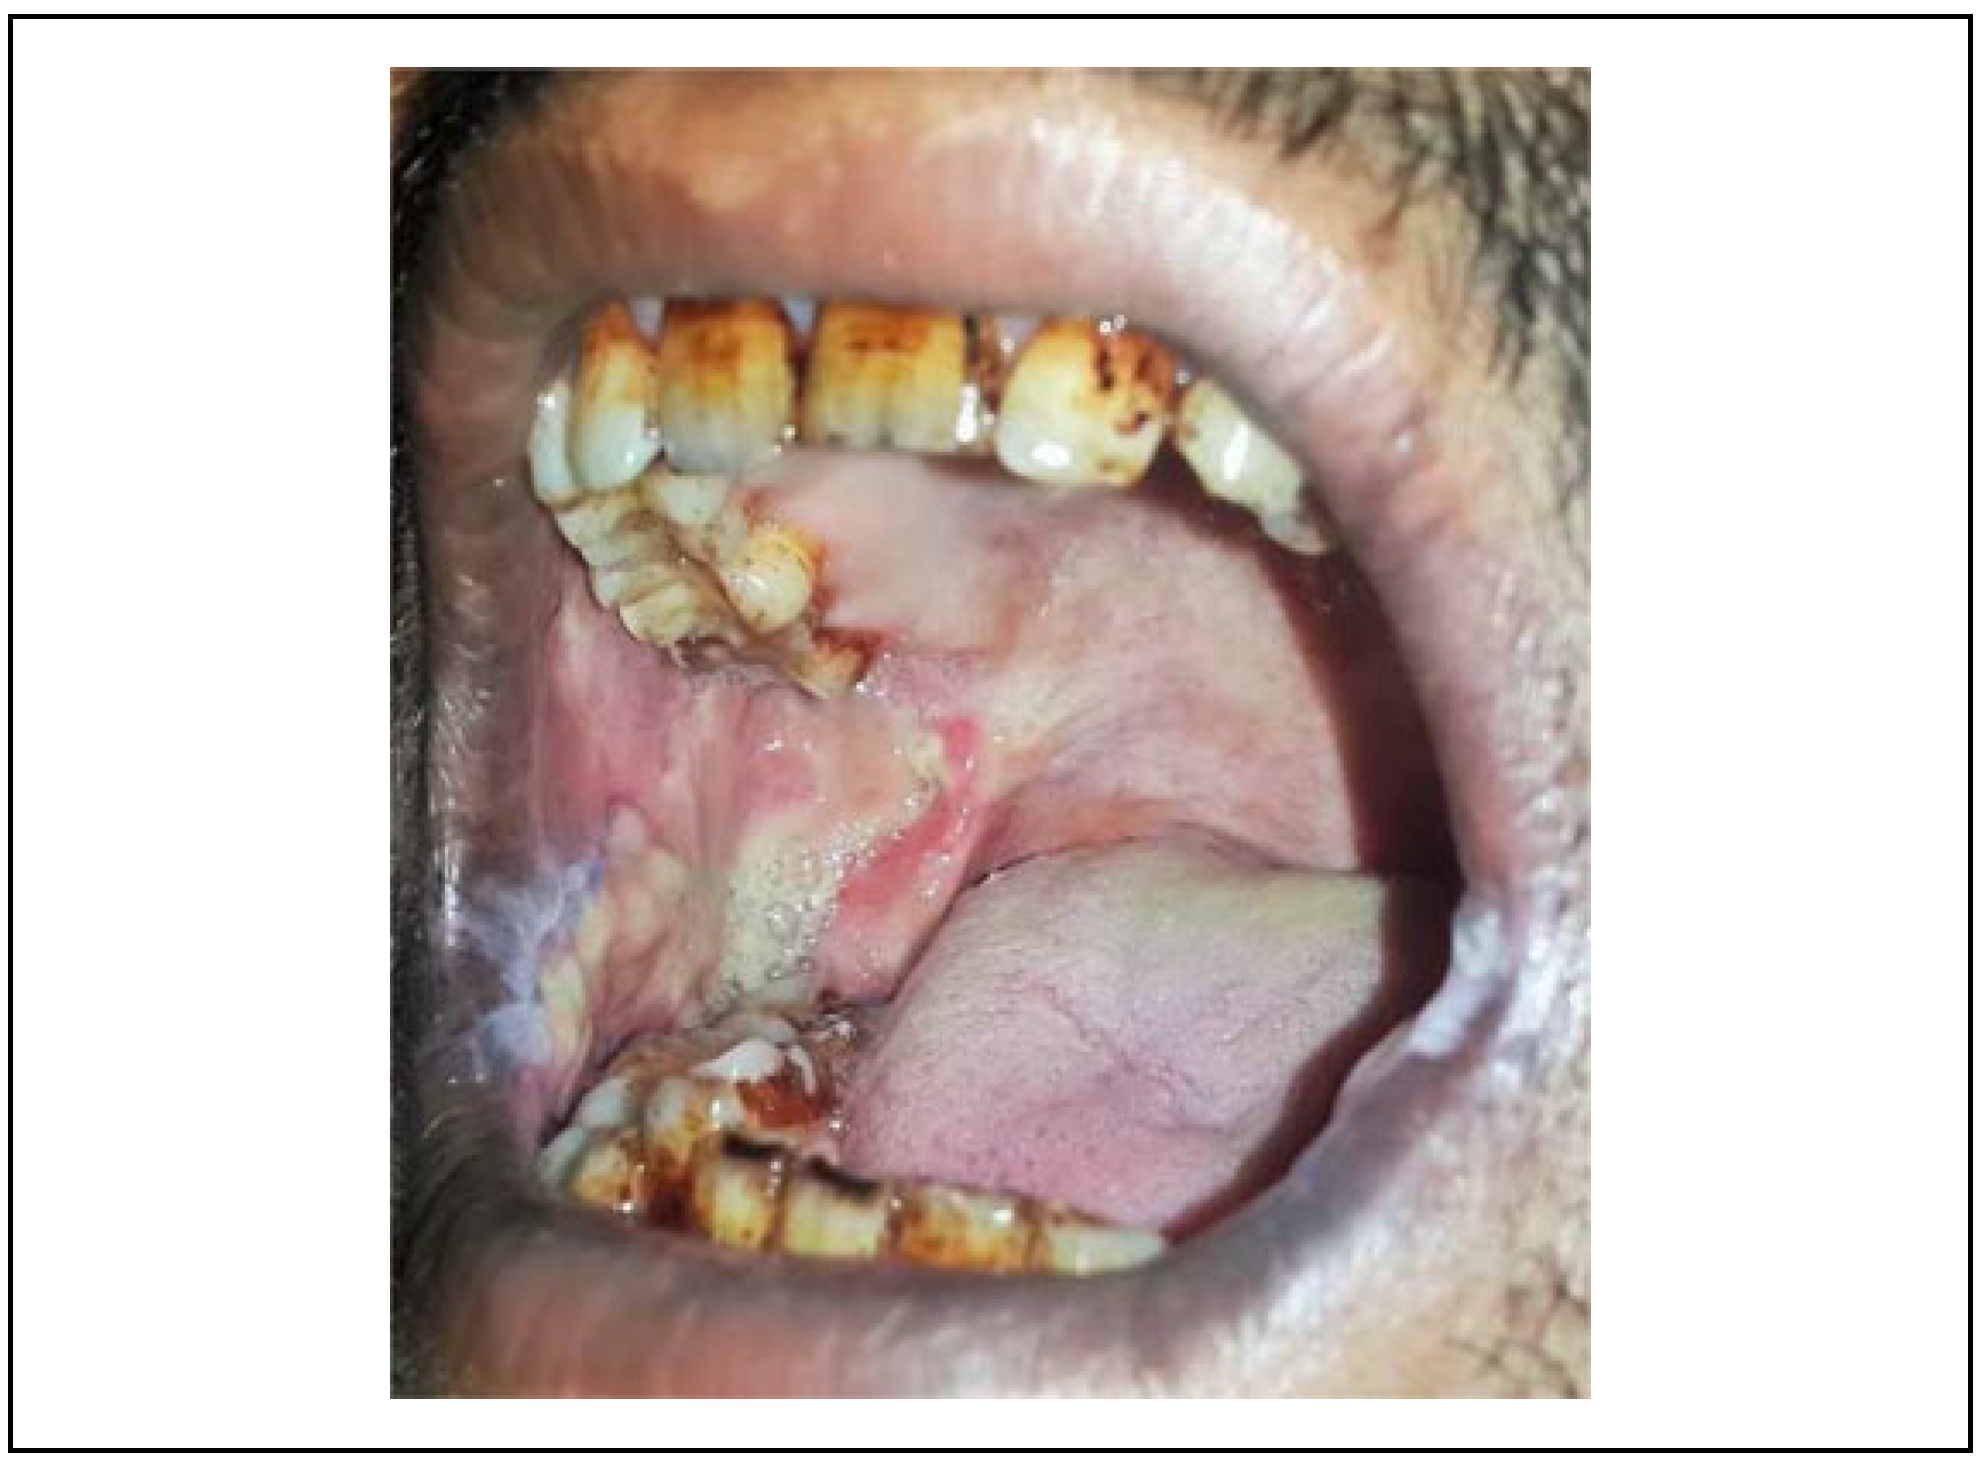

The use of the NLF, in OSMF treatment, is more suitable for juxtaposed defects, particularly those of the buccal mucosa.[6] Therefore, this flap is becoming increasingly popular. The NLF is a good example of the transposition flap principle.[10] The satisfactory result of NLF for OSMF is because flap itself is not a part of the crippled oral disease. In this study, bilateral centrally based pedicled single stage flap was used without any second surgery for revision. The literature suggests that the NLF is a superior reconstructive option for patients with OSMF in terms of blood supply, adaptability to the defect (Figure 5), and versatility.[3,6,10]

Other studies have reported the following drawbacks of the NLF: extraoral scars and hair growth in male patients. So, in this study, we assessed extraoral scar formation and the patient’s perception. The assessment revealed a satisfactory outcome after 1-year follow-up, even though the temporary widening of oral commissure was observed. It is prudent to counsel the patient going in for NLF about the extraoral scar and weighing the benefits on a long-term basis. In our study, all patients accepted the scar without any significant complaints. The hair growth, although seen in the early postoperative period, was reduced during the follow-up period of 1 year. In NLF group, there was good coverage of raw area following fibrotomy in the early phase of post-surgery and at 1-year follow-up there was appreciable margin adaptation with no evidence of contracture with smooth pliable soft tissue in the reconstructed area. Whereas in BFP group, there was deficient coverage (25%-30%) of raw area and at 1-year follow-up there was evidence of contracture and secondary fibrosis on palpation.

Figure 5. NLF with good cover and adaptation to the surgical defect. NLF indicates nasolabial flap.